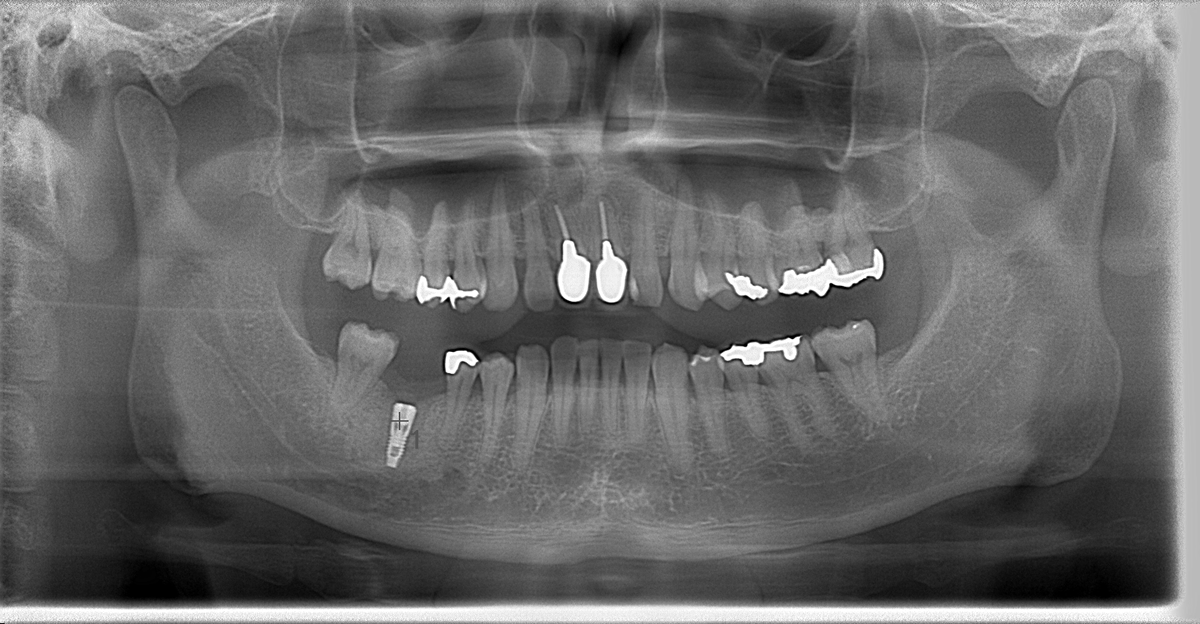

このように歯を失ってしまいお悩みの方に、当院では新しい治療法「インプラント治療」をご案内しております。

インプラント治療とは、失ってしまった自分の歯の替わりに、人工の歯根を顎の骨に埋め込み、その上に人工の歯を作製して噛み合わせを回復する治療法です。

インプラント治療に必要な診査を行いインプラントの治療が可能かどうかを診断してもらいます。その後、治療計画を立てます。

人工歯根(=フィクスチャー)を手術により顎の骨を埋入れする手術を行います。必要があれば骨を移植する場合もあります。局所麻酔を用いて行いますので安心して手術を受けることができます。当院では傷の治りを良くするために、手術前に採血を行い、専用の遠心分離器でCGFを得ます。CGFとは血小板とフィブリンを多く含んだゲル状のものです。それを潰し、膜状にしたものを埋入れしたインプラントの上に乗せ、歯肉を閉じると治りも早くなります。

この後、骨とインプラントがしっかり結合されるまでの治癒期間を設けます。(3~6カ月)

人工歯の支台となるインプラントの部品(=アバットメント)をフィクスチャーに連結します。

インプラントを含めたお口の中全体の印象採得(=型を取ること)を行います。その型に従い人工の歯を作成します。その後、アバットメントの上に人工歯を装着して完成です。

インプラント治療の終了後、インプラントを長持ちさせるためには適切なホームケアと定期的な検診が必要です。インプラントの本数やお口の中の状態により1か月~半年に1度、定期検診と歯のクリーニングを行います。

右下6が欠損で右下6に1本埋入れする手術を行うと(4.5 11㎜ 1本)

125,000円(埋入手術)+47,000円(4.5 11㎜)となります。

さらに骨移植・GBRを行うと30,000円の加算。ここまでがインプラントの埋入手術の料金になります。

当医院は2003年からインプラント治療を開始し、現在では年間約50~60本のインプラント手術を行っております。(2017年実績)約14年間で累計約800本のインプラント治療を行い、過去の手術で13本のインプラントが脱落しておりますが、再手術をして現在では問題なく使用しております。